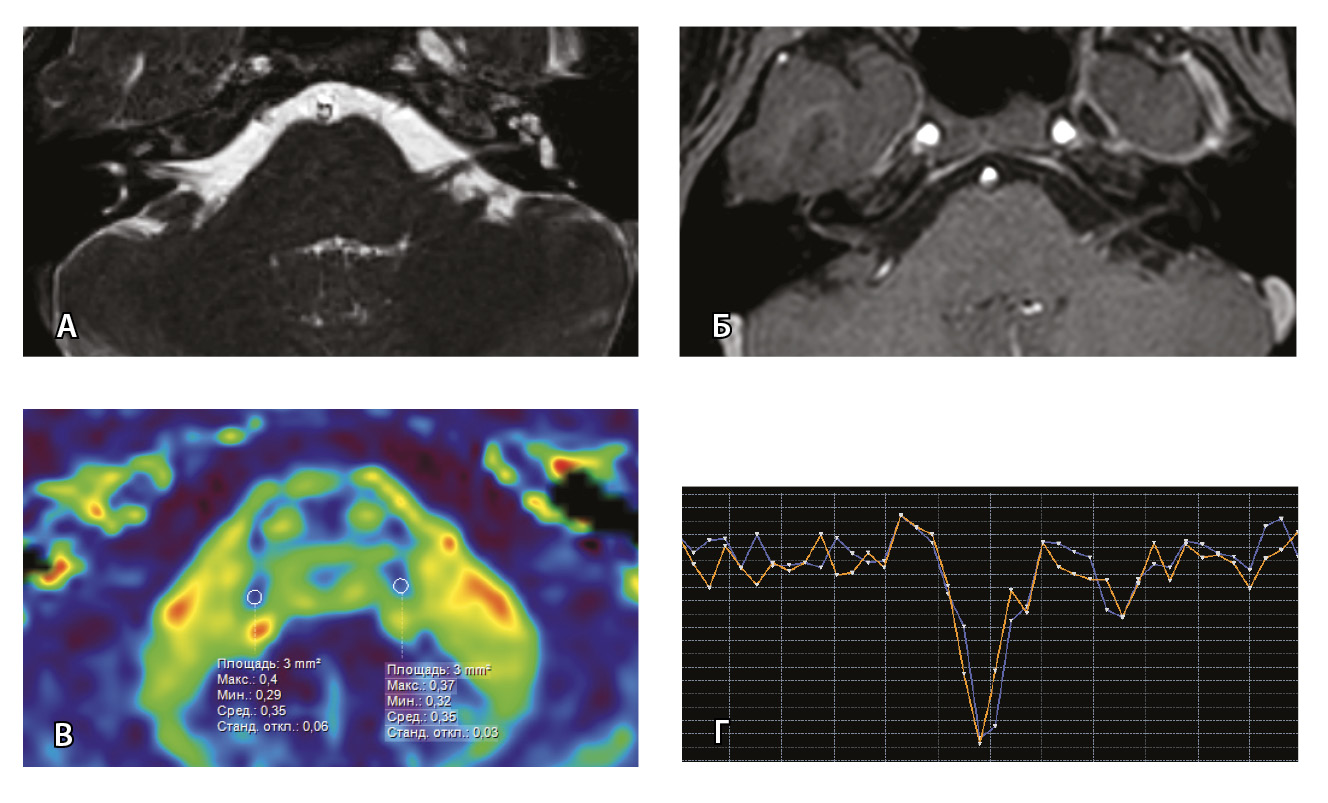

Рис. 7. Клиническое наблюдение 2, пациент 6 лет (А, Б, В, Г). Магнитно-резонансная томография (МРТ) головного мозга: А – прицельная T2-SSFP на область мосто-мозжечкового угла; Б – Т1-взвешенное изображение с контрастным усилением; В – диффузионно-тензорная МРТ (фракционная анизотропия, ФА); Г – Т2*-перфузия. На изображении T2-SSFP отмечается утолщение корешков лицевого, вестибуло-кохлеарного нервов во внутренних слуховых проходах (А, желтые стрелки) и интенсивное накопление ими контрастного вещества (Б, красные стрелки). На уровне моторных ядер лицевых нервов в заднем отделе варолиевого моста значения ФА симметричны (В), признаков гипо-/гиперперфузии не выявлено (Г).

Клиническое наблюдение 3, пациент 13 лет (Д, Е, Ж, З). МРТ головного мозга: Д – прицельная T2-SSFP на область мосто-мозжечкового угла; Е – Т1-взвешенное изображение с контрастным усилением; Ж – диффузионно-тензорная МРТ (ФА); З – Т2*-перфузия. На изображении T2-SSFP патологические изменения на уровне прохождения лицевых нервов во внутренних слуховых проходах не определяются (Д). В медиальном отделе правого полушария мозжечка определяется объемное образование, компримирующее стенку IV желудочка и задний отдел варолиевого моста без признаков васкуляризации (Е). На уровне моторных ядер лицевого нерва в заднем отделе варолиевого моста на изображениях ФА на стороне поражения отмечается минимальное уменьшение показателя ФА до 0,27 (Ж, черная стрелка) и признаки гипоперфузии (З, оранжевый график) по сравнению с контралатеральной стороной (З, синий график)